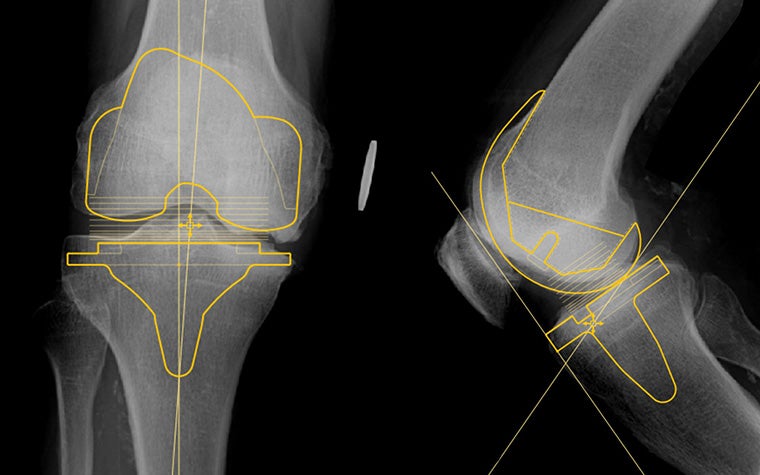

Join this training course for a quick start in digital templating using one of the most trusted planning tools in the market, Materialise OrthoView, which has a 96% planning accuracy in THA. You'll learn how to perform the most optimal workflows for planning total hip replacement and total knee replacement procedures.

- How to scale X-ray images, analyze biomechanics, and template for knee and hip replacement

It will give you the foundation to learn templating using X-ray scaling, analysis tools, and smart templates.